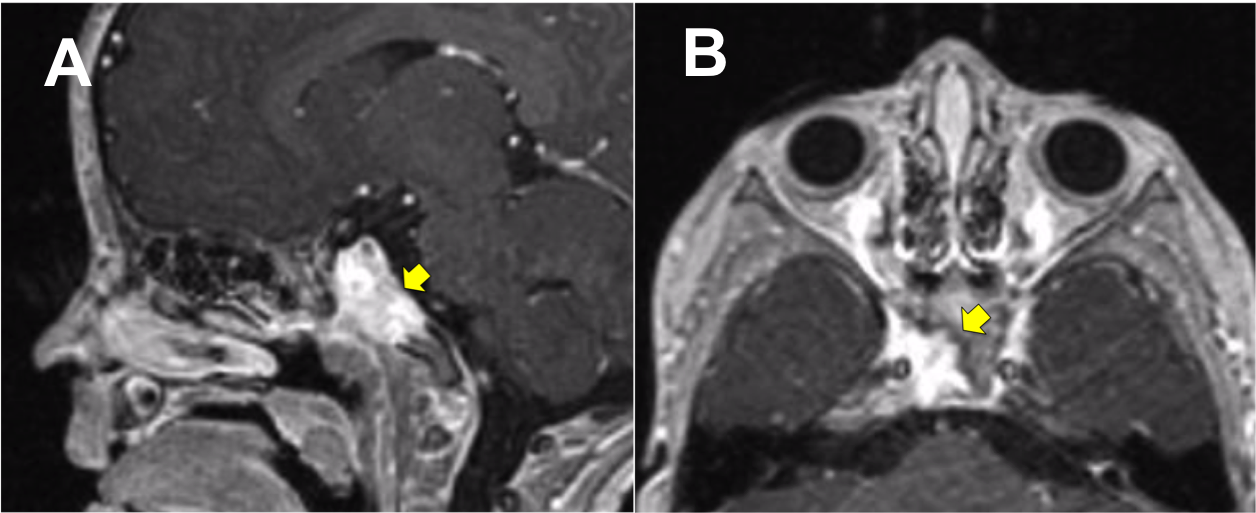

Introducción: La cirugía endoscópica endonasal se ha convertido en una herramienta fundamental para el manejo de patologías que comprometen la base de cráneo. En casos bien seleccionados, estas técnicas permiten resecciones quirúrgicas con una menor morbilidad sin comprometer los principios oncológicos de resección. Con el desarrollo de instrumental especializado, nuevas tecnologías y la experiencia de los cirujanos, la cirugía endoscópica endonasal se usa cada vez más en cirugía de base de cráneo en niños.

Diseño: Estudio observacional descriptivo de tipo serie de casos. Metodología: se describe la experiencia con pacientes pediátricos llevados a cirugía endoscópica endonasal para manejo de tumores de base de cráneo en el Instituto Nacional de Cancerología entre julio de 2014 y diciembre de 2016.

Resultados: Fueron intervenidos 8 pacientes entre los 2 y 14 años, con una edad promedio de nueve años y un seguimiento promedio de 16 meses. En el 75% se hizo una resección total del tumor. Un paciente requirió una reintervención y un paciente fue sometido a radiocirugía post-operatoria. 1 paciente falleció a pesar de múltiples intervenciones, quimioterapia y radioterapia.

Conclusión: La cirugía endoscópica endonasal para tumores de base de cráneo puede ser utilizada de forma segura en los pacientes pediátricos, es una técnica que en casos bien seleccionados pueden ofrecer excelentes resultados disminuyendo la morbilidad y complicaciones de las técnicas abiertas.